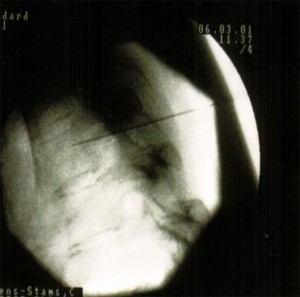

Para visualizar el sitio de punción se coloca el arco de fluoroscopia rayo en posición PA y se ubica en el centro de la imagen el espacio intervertebral del nivel que se desea alcanzar. Luego se mueve el arco de fluoroscopia en el plano axial para eliminar el doble contorno del borde inferior de la vértebra. Después de fijar el rayo se dan aproximadamente 25°-30° de inclinación oblicua hacia el lado que se va a intervenir, hasta que el foramen, que está por debajo del pedículo, se visualice como un círculo homogéneo. En esta imagen se apreciarán también las costillas y las articulaciones costovertebrales.

El punto de entrada se marca en el foramen que se visualiza debajo del pedículo, que sería el sitio de salida de la raíz. Se infiltra el punto de entrada con 5-10 ml de lidocaína al 1%. A través de este punto se avanza una aguja 22G de 10 cm, siempre en túnel visión. La aguja irá medial a la costilla y a la articulación costovertebral, y lateral al borde de la lámina.

Para confirmar la posición de la aguja se posiciona el arco de fluoroscopia rayo en lateral. Ésta debe alcanzar la región media o posterior del foramen en esta proyección.

Finalmente se rota el arco de fluoroscopia hasta la posición PA, la aguja no debe estar más medial de las 6:00 con respecto al pedículo. Se inyectan 1-2 ml de contraste para confirmar que la aguja está en la raíz , en la placa se debe observar la raíz dorsal y el espacio epidural.